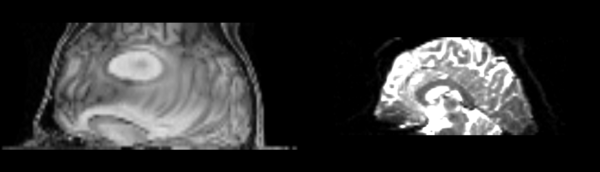

Bspline Only

Though it has been recommended to always go through a pipeline before using a non-linear registration, We've given a B-spline only registration a try. This is Slicer 3's separate Bspline module. Unsurprisingly, it works extremely poorly. The brain is barely recognizable any longer, with strange curvatures at the top, gross enlargement of the middle third (S-I) and unclear registration along the very bottom, stretching out along the entire image.

Diffeomorphic Demons

The image has been expanded radially outward, not clearly matching to any features of the DTI baseline.

Linear to Affine to Bspline

As suggested, in this test we registered the image via linear, then affine, then bspline modules in Slicer 3. Again the registration is largely incomprehensible.

Pipeline B-spline

Curved crazily, still doesn't appropriately fit.